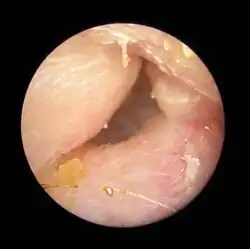

| Exostoses in the ear canal, as seen through otoscopy | |

Surfer's ear is the common name for an exostosis or abnormal bone growth within the ear canal. They are otherwise benign hyperplasias (growths) of the tympanic bone thought to be caused by frequent cold-water exposure.[1] Cases are often asymptomatic.[1] Surfer's ear is not the same as swimmer's ear, although infection can result as a side effect.

Irritation from cold wind and water exposure causes the bone surrounding the ear canal to develop lumps of new bony growth which constrict the ear canal. Where the ear canal is actually blocked by this condition, water and wax can become trapped and give rise to infection. The condition is so named due to its high prevalence among cold water surfers, although it can occur in any water temperature due to the evaporative cooling caused by wind and the presence of water in the ear canal.